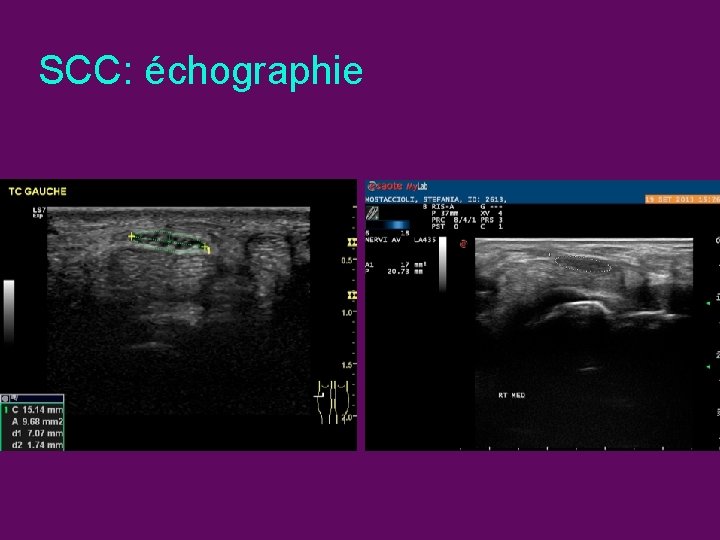

SCC: échographie